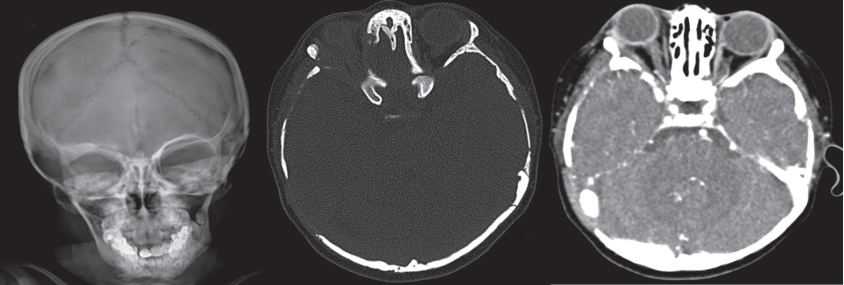

Radiografía simple y tomografía de cráneo con reconstrucciones axiales en ventana ósea; lesiones líticas que involucran el ala menor del esfenoides derecho y los huesos temporal y occipital del lado derecho. La fase contrastada al mismo nivel muestra engrosamiento de tejidos blandos con reforzamiento moderado.

Cortes en secuencia T1 de resonancia magnética con gadolinio que muestran aumento de tamaño de los plexos coroideos, con reforzamiento moderado. En la exploración dirigida a órbitas se logra identificar compromiso del ala menor del esfenoides derecho.

Reconstrucción sagital en secuencia FLAIR de resonancia magnética que muestra ocupación de silla turca por líquido cefalorraquídeo que desplaza en sentido posterior la glándula hipófisis.